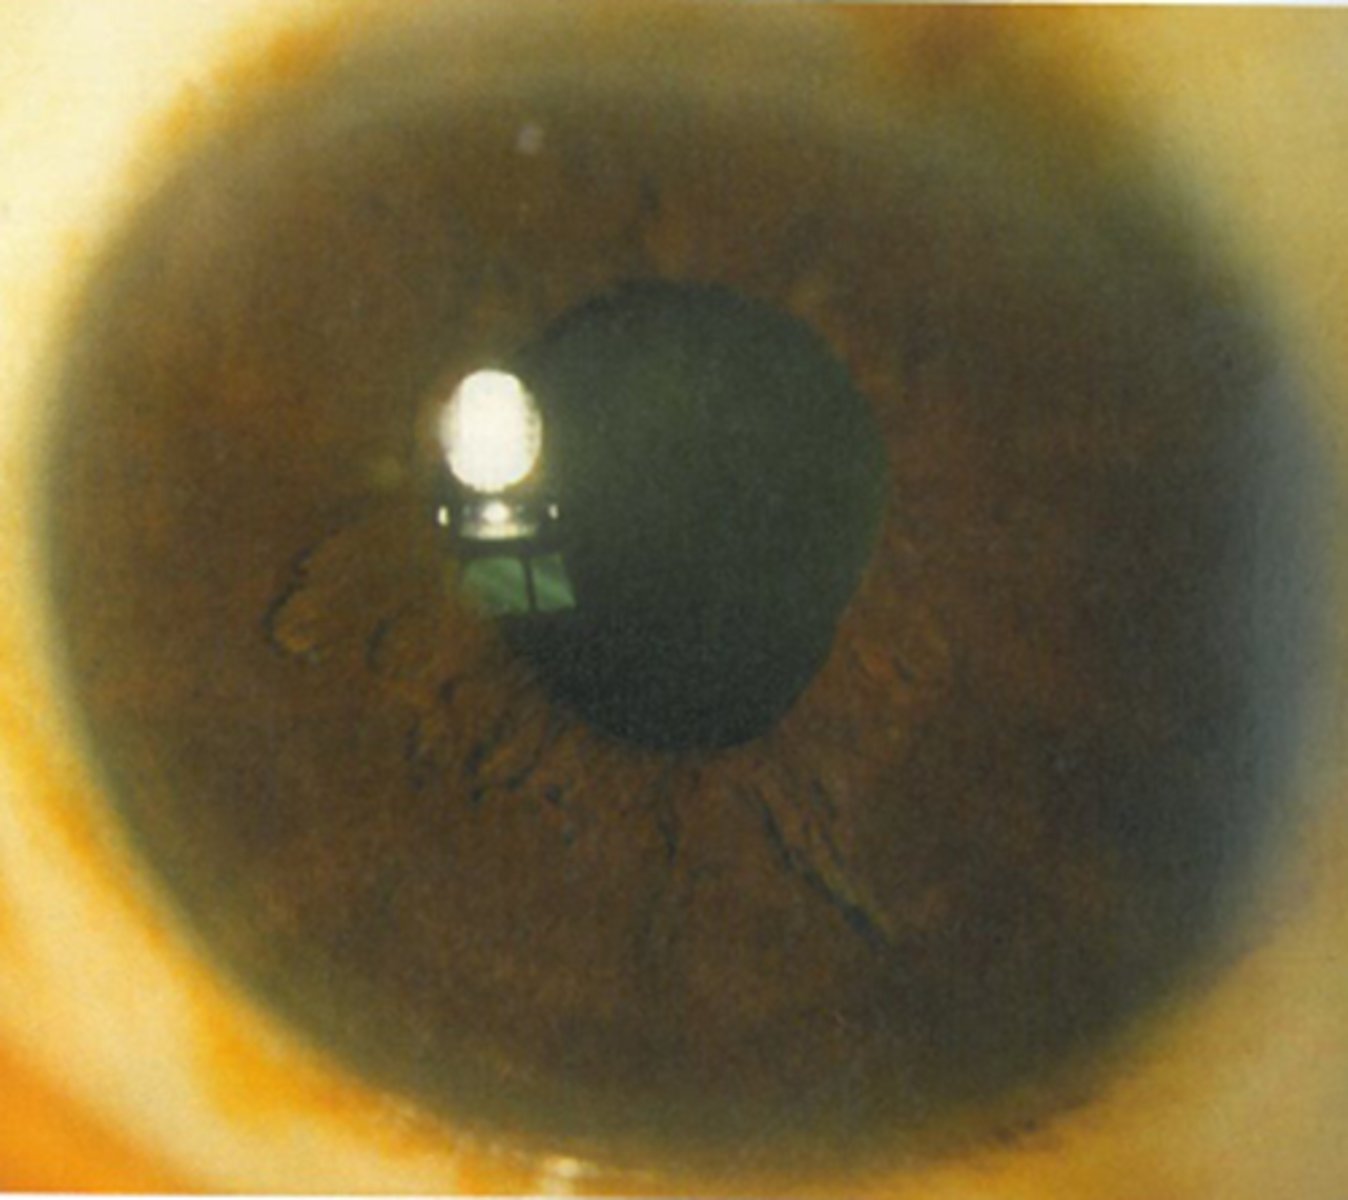

What are the 4 S's that we expect to see when looking at the size and shape of a tonic pupil?

sector paralysis = abnormal shape due to sphincter/dilater paralysis

stromal spread = iris stroma spreads due to lack of innervation

pigment stream entropion = pupil border of iris is entropic adjacent to a part of the pupil border that is more flat

stromal streaming = stroma flows towards area that sphincter still works when light is turned on